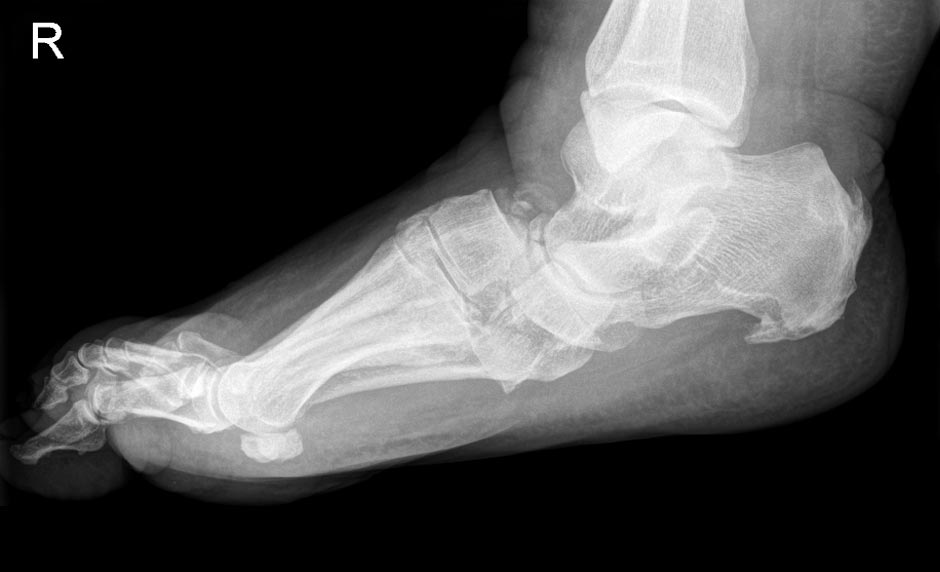

A.L., w., 58 Jahre, Vorerkrankungen: Diabetes mellitus, periphere Polyneuropathie und Adipositas per magna litt unter einer diabetischen Osteoarthropathie (Charcotfuß) mit kompletter Luxation der Fußwurzel. Aufgrund Rollstuhlpflicht und immobilisierender Schmerzen Indikation zur kompletten Fußwurzelkorrekturarthrodese mit Mittelfußbolzen. 6 Monaten postoperativ schmerzfrei im orthopädischen Schuh ohne Gehstützen mobil.